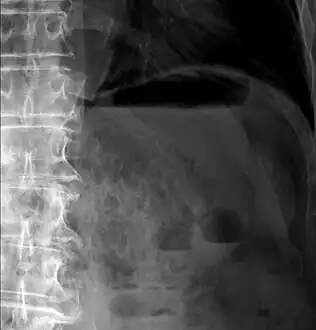

Pneumatosis intestinalis in computed tomography with intestinal ischemia. Lung window for better representation of the gas deposits in the intestinal walls.- Upright AP radiograph showing gas in the wall of the small bowel in the left upper quadrant indicative of pneumatosis intestinalis.